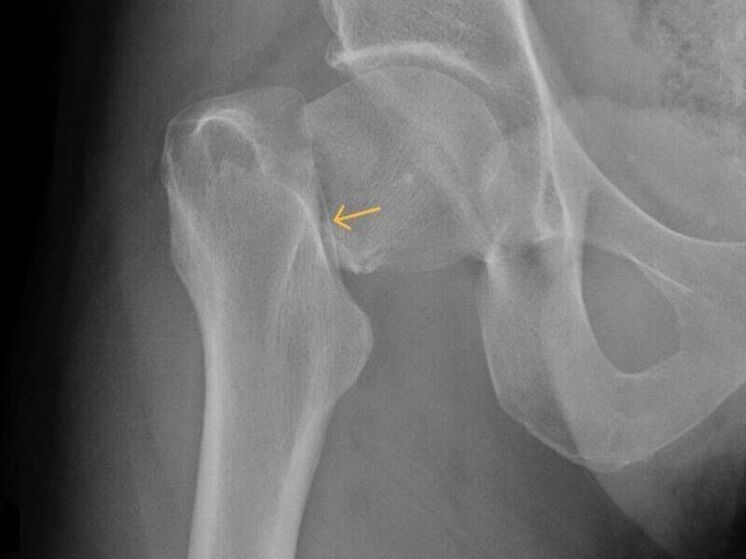

В Новокузнецке врачи городской больницы имени Г.П. Курбатова допустили грубую ошибку — не распознали у пациента перелом шейки бедра. После обращения мужчины, получившего травму при падении на улице, медики ограничились поверхностным осмотром и поставили неверный диагноз — «растяжение связок».

Несмотря на сильную боль, мужчине назначили амбулаторное лечение, а вскоре и вовсе закрыли больничный лист, направив его обратно на работу. Симптомы тем временем усиливались, и лишь спустя полтора месяца компьютерная томография показала — у пациента тяжёлый перелом.